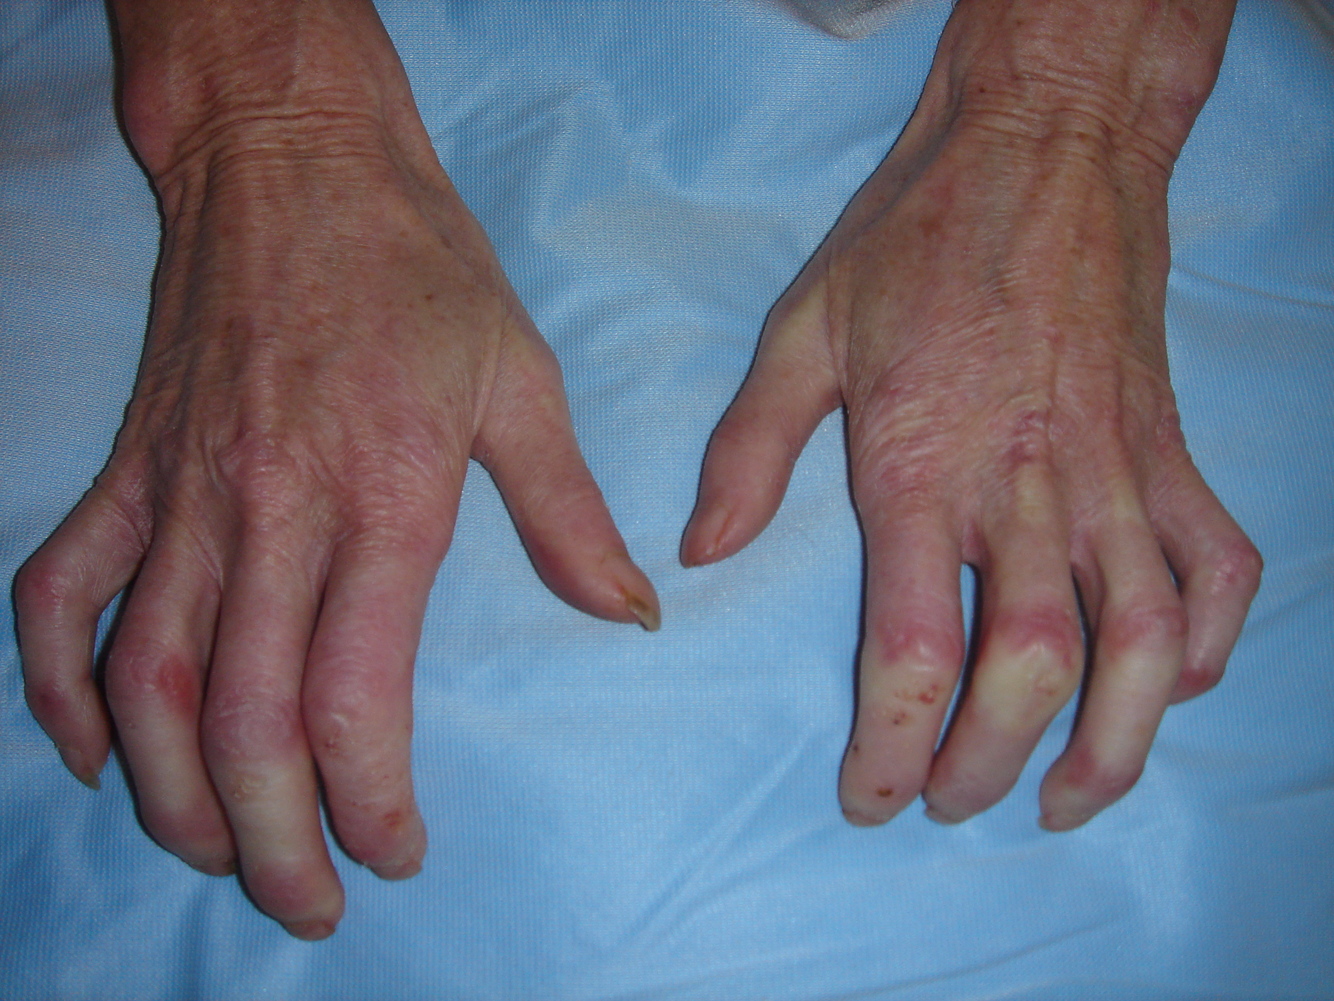

Inflammatory Arthritide: - Symmetrical distribution - Bilateral uniform loss of joint space - Rat Bite erosions - Pannus formation - Localized periarticular osteoporosis - DIP’s spared - Atlanto-axial instability - Haygarth’s Nodes @ MCP (knuckle) - Swan Neck / Boutonniere deformity - Ulnar/Fibular deviation (Lanois) of fingers/toes

Rheumatoid Arthritis (RA)